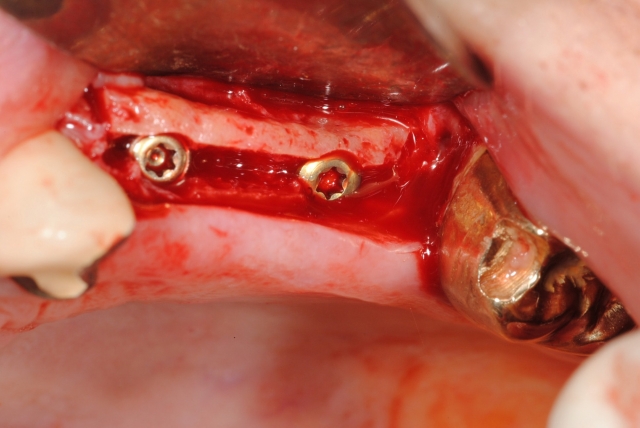

Moreover, if you want greater interproximal attached tissue to increase papillae, turn the cross 45 degrees and make diagonal incisions so that the flaps are mesial and distal (Fig. 1c). The buccal flap can be left as is or removed with a diode laser if there is excessive buccal tissue. If there is ample attached tissue but you are unclear about exact implant placement or have multiple implants to uncover, then you may make a midcrestal incision and expose the implant site(s) (Fig. 2).